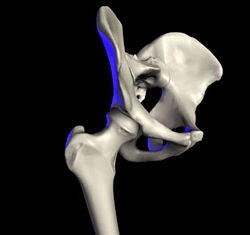

The hip joint is reinforced by four ligaments, of which three are extracapsular and one intracapsular.

The extracapsular ligaments are the iliofemoral, ischiofemoral, and pubofemoral ligaments attached to the bones of the pelvis (the ilium, ischium, and pubis respectively). All three strengthen the capsule and prevent an excessive range of movement in the joint. Of these, the Y-shaped and twisted iliofemoral ligament is the strongest ligament in the human body.[22] In the upright position, it prevents the trunk from falling backward without the need for muscular activity. In the sitting position, it becomes relaxed, thus permitting the pelvis to tilt backward into its sitting position. The iliofemoral ligament prevents excessive adduction and internal rotation of the hip. The ischiofemoral ligament prevents medial (internal) rotation while the pubofemoral ligament restricts abduction and internal rotation of the hip joint.[23] The zona orbicularis, which lies like a collar around the most narrow part of the femoral neck, is covered by the other ligaments which partly radiate into it. The zona orbicularis acts like a buttonhole on the femoral head and assists in maintaining the contact in the joint.[22] All three ligaments become taut when the joint is extended - this stabilises the joint, and reduces the energy demand of muscles when standing.[24]

The intracapsular ligament, the ligamentum teres, is attached to a depression in the acetabulum (the acetabular notch) and a depression on the femoral head (the fovea of the head). It is only stretched when the hip is dislocated, and may then prevent further displacement.[22] It is not that important as a ligament but can often be vitally important as a conduit of a small artery to the head of the femur, that is, the foveal artery.[25] This artery is not present in everyone but can become the only blood supply to the bone in the head of the femur when the neck of the femur is fractured or disrupted by injury in childhood.[26]